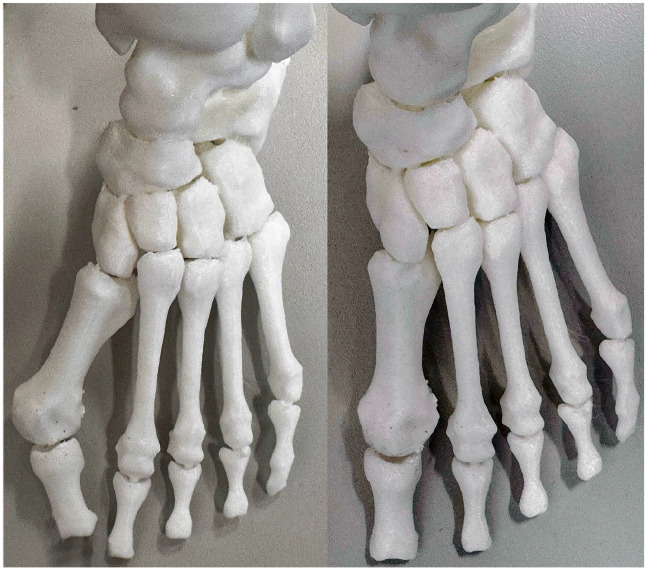

Background: Recent literature highlights the importance of treating hallux valgus (HV) as a 3-dimensional (3D) deformity. Although 3D printing may enhance visualization of the multiplanar aspects of HV, its influence on surgical planning remains unclear. This study assessed changes in surgical plans when surgeons sequentially reviewed 2D radiographs, 3D weightbearing computed tomography (WBCT), and 3D-printed models, hypothesizing that 3D printing would have the greatest impact.

Methods: A single HV case (a 40-year-old woman, intermetatarsal angle [IMA] 21 degrees, HV angle [HVA] 47 degrees) was evaluated by 30 surgeons in a masked, stepwise manner. Surgical plans were recorded at each stage. Surgeons rated the influence of WBCT and 3D printing using a 5-point Likert scale. A follow-up survey examined the effect of these technologies on correction amplitudes.

Abstract Image